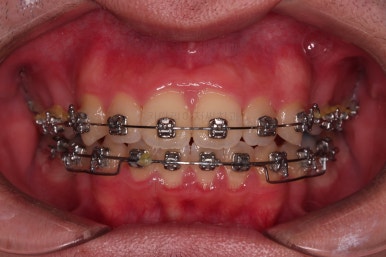

총 19개월만에 치료를 종료했습니다.

가지런한 느낌, 교합, 중앙선 등 매우 양호한 치료결과였습니다.

전후 비교입니다.

입은 약간만 들어가게끔 했고요.

웃을 때의 입매가 참 좋아졌네요.

얼굴모습에서 드러나는 치열의 느낌이 매우 좋아졌어요.